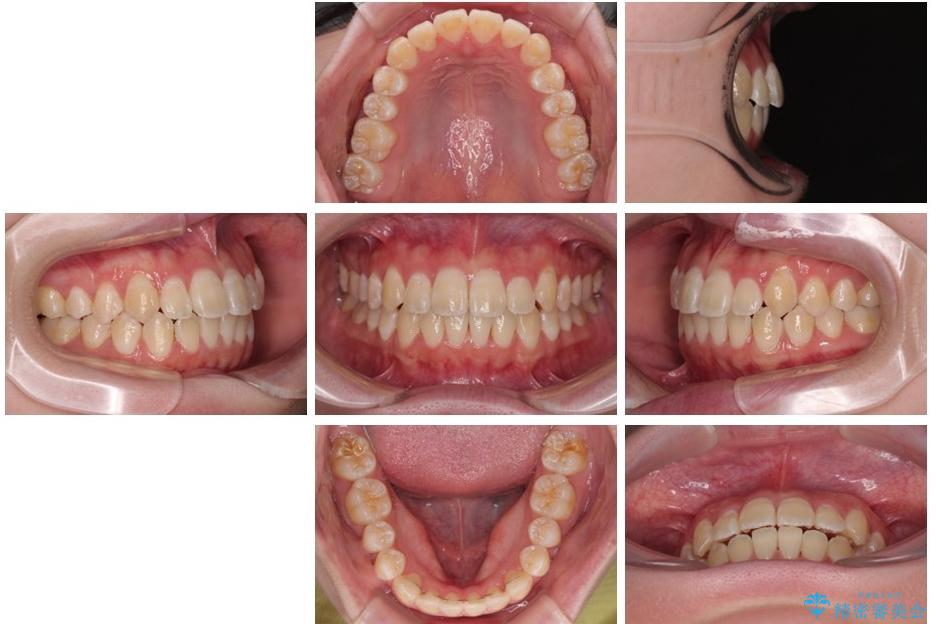

「前歯のデコボコ(叢生)をきれいに整えたい」とのことでご来院されました。

マウスピース矯正も検討されていましたが、「装着時間の自己管理が難しそう」「なるべく早く治療を終えたい」とのご希望から、ワイヤー矯正を選択されました。

上下の正中(真ん中のライン)もずれることなく、バランスの取れた美しい歯並びに。笑顔に自信を持てる仕上がりとなりました。

治療前

• 【モニター】前歯のデコボコをスッキリ解消!目立ちにくいワイヤー矯正でスピーディに治療完了 治療前画像

治療後

• 【モニター】前歯のデコボコをスッキリ解消!目立ちにくいワイヤー矯正でスピーディに治療完了 治療後画像